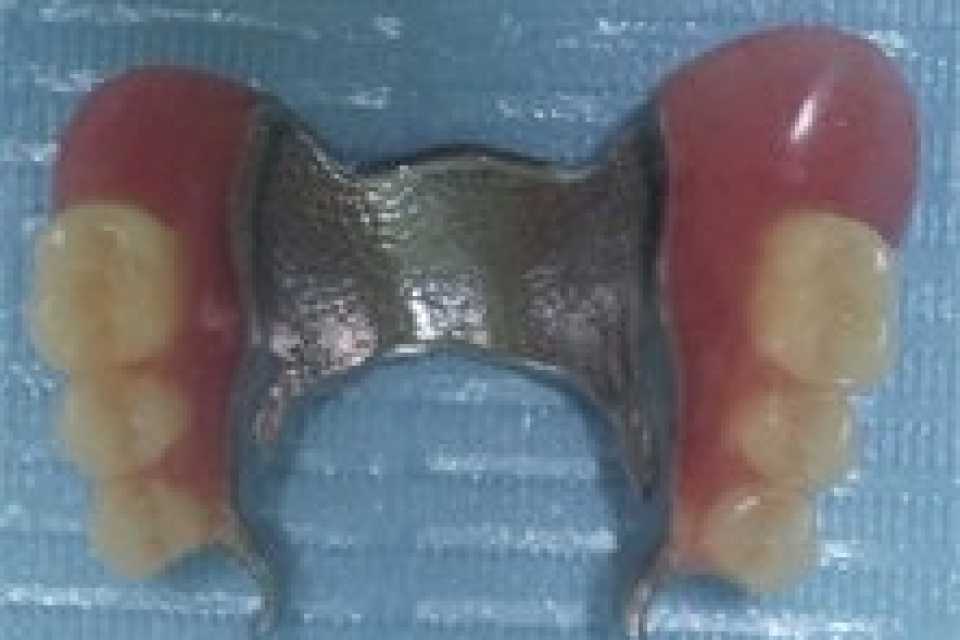

Proteza scheletata superioara pe telescoape si inferioara pe capse

Cazul 21: Proteze scheletate cu sisteme speciale de prindere